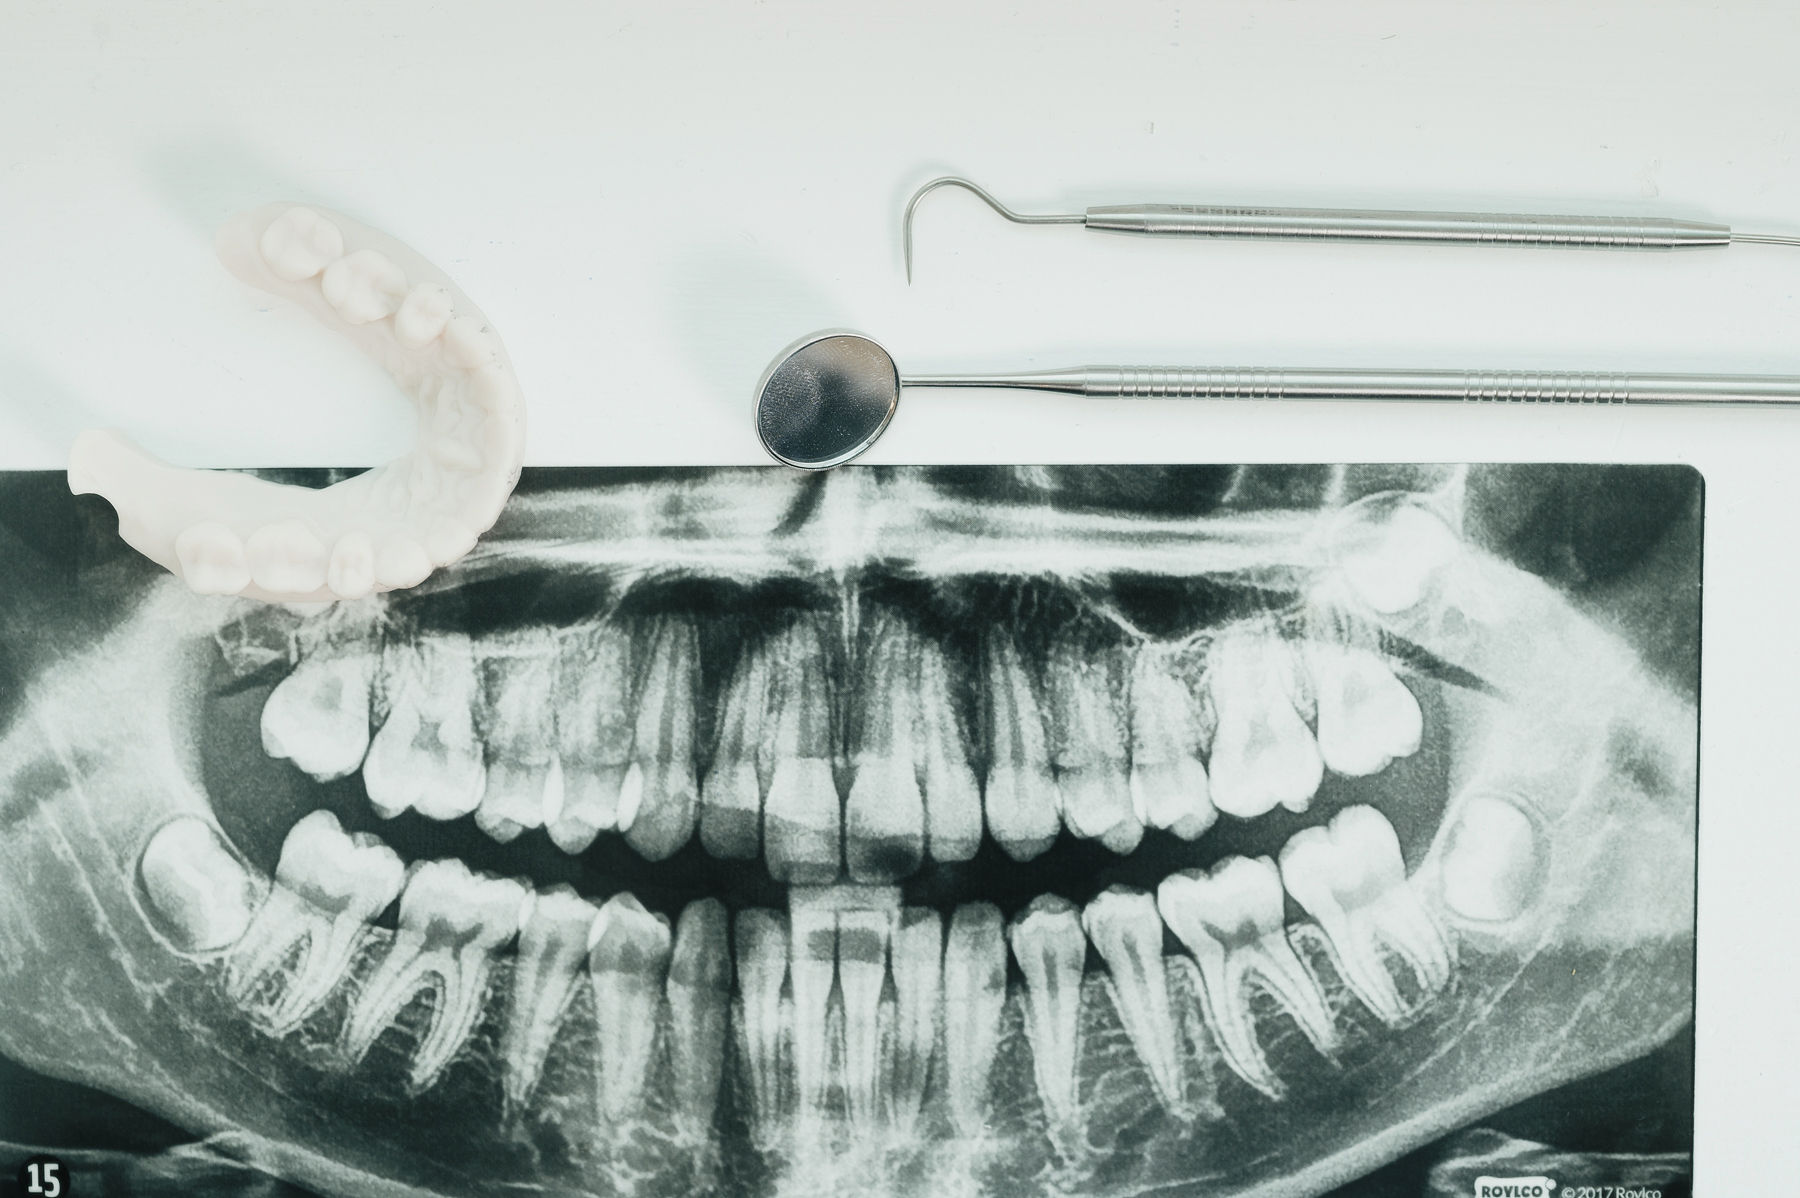

Wisdom teeth, also known as third molars, are the last teeth to develop, typically appearing in the late teenage years or early adulthood. Because many patients do not have enough space in the jaw to accommodate these additional molars, wisdom teeth often become impacted or only partially erupt through the gums. When this occurs, they may contribute to infection, damage nearby teeth, create cysts, or lead to long-term changes in bite alignment and oral health.

Early evaluation of wisdom teeth allows surgeons to identify potential problems before pain, infection, or damage to surrounding teeth develops. In many cases, removing problematic wisdom teeth early can help prevent more complex issues later and support healthier long-term outcomes..

Compassion leads the way for our team to support and guide you every step of the way. Through advanced diagnostics with digital imaging and 3D scans, we ensure precision planning and tailored solutions based on your unique anatomy for a seamless procedure.